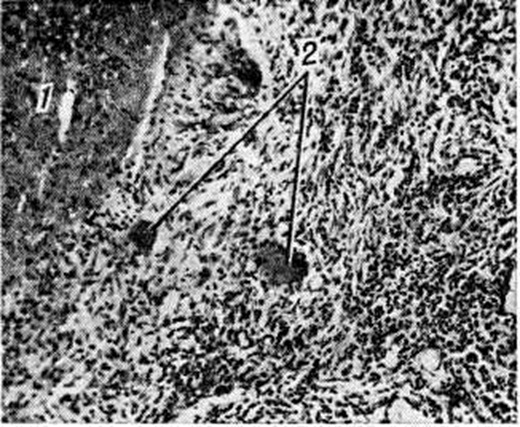

Морфология туберкулёзного воспаления отличается большим разнообразием. В зависимости от реактивности организма (смотри полный свод знаний) и вирулентности возбудителя в туберкулёзном очаге могут преобладать явления экссудации (смотри полный свод знаний), некроза (смотри полный свод знаний) или пролиферации (смотри полный свод знаний), и очаг в соответствии с этим может быть преимущественно экссудативным, некротическим или продуктивным. По данным В. И. Пузик (1966) и А. И. Струкова (1981), в развитии туберкулёзного воспаления большая роль принадлежит иммунным процессам. Поэтому оно является классическим примером воспаления (смотри полный свод знаний), протекающего на иммунной основе. В участке воспаления вначале развивается банальная реакция, не имеющая признаков, типичных для Туберкулёз В ней в разной степени выражены явления альтерации и экссудации. В следующей фазе воспалительной реакции — пролиферативной — появляются специфические для Туберкулёз элементы (эпителиоидные и гигантские клетки Пирогова — Лангханса), формируются участки своеобразного гомогенного казеозного (творожистого) некроза в центре туберкулёзного очага (рисунок 2). Эпителиоидные клетки образуются из гистиоцитов и макрофагов, скапливающихся в очаге туберкулёзного воспаления в первые фазы воспалительной реакции. Они имеют крупное светлое овальной формы ядро, обычно с одним — двумя крупными ядрышками. Цитоплазма этих клеток содержит РНК в виде мелких зёрен, что свидетельствует о их функциональной активности, а также хорошо развитую систему канальцев и цистерн зернистой и незернистой эндоплазматической сети, везикул комплекса Гольджи (смотри полный свод знаний: Гольджи комплекс), в тесной связи с которым находятся лизосомы (смотри полный свод знаний). Количество митохондрий, лизосомальных включений и фагосом варьирует.

Туберкулёзные гранулемы имеют округлую форму, размеры их достигают величины зёрен проса (просовидные бугорки), но могут быть и несколько крупнее. В зависимости от реактивности организма гранулемы могут быть экссудативными, состоящими преимущественно из лимфоидных клеток, экссудативно-продуктивными, продуктивными и некротическими; последние встречаются при резком угнетении защитных сил организма. Типичные продуктивные туберкулёзные гранулемы состоят из эпителиоидных клеток и гигантских клеток Пирогова — Лангханса, а также расположенных по периферии лимфоидных клеток. Иногда в центре гранулемы формируется участок казеозного некроза. При импрегнации серебром (смотри полный свод знаний: Серебрения методы) в гранулеме вне гигантских клеток выявляются аргирофильные волокна (рисунок 3). Гранулемы могут сливаться, образуя очаги, в которых различаются элементы стромы отдельных составляющих их гранулем. При заживлении клеточные элементы частично рассасываются и на месте гранулемы развивается небольшой рубчик неправильной паукообразной формы.